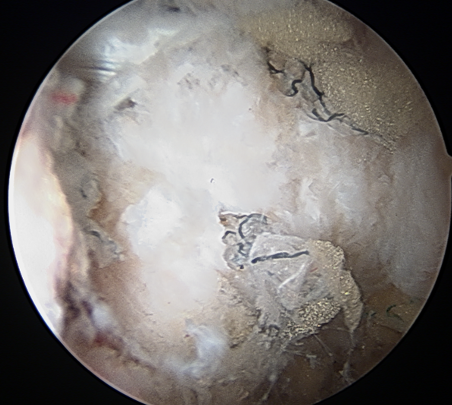

Heterotopic ossification - 1%

Heterotopic ossification anterior capsule